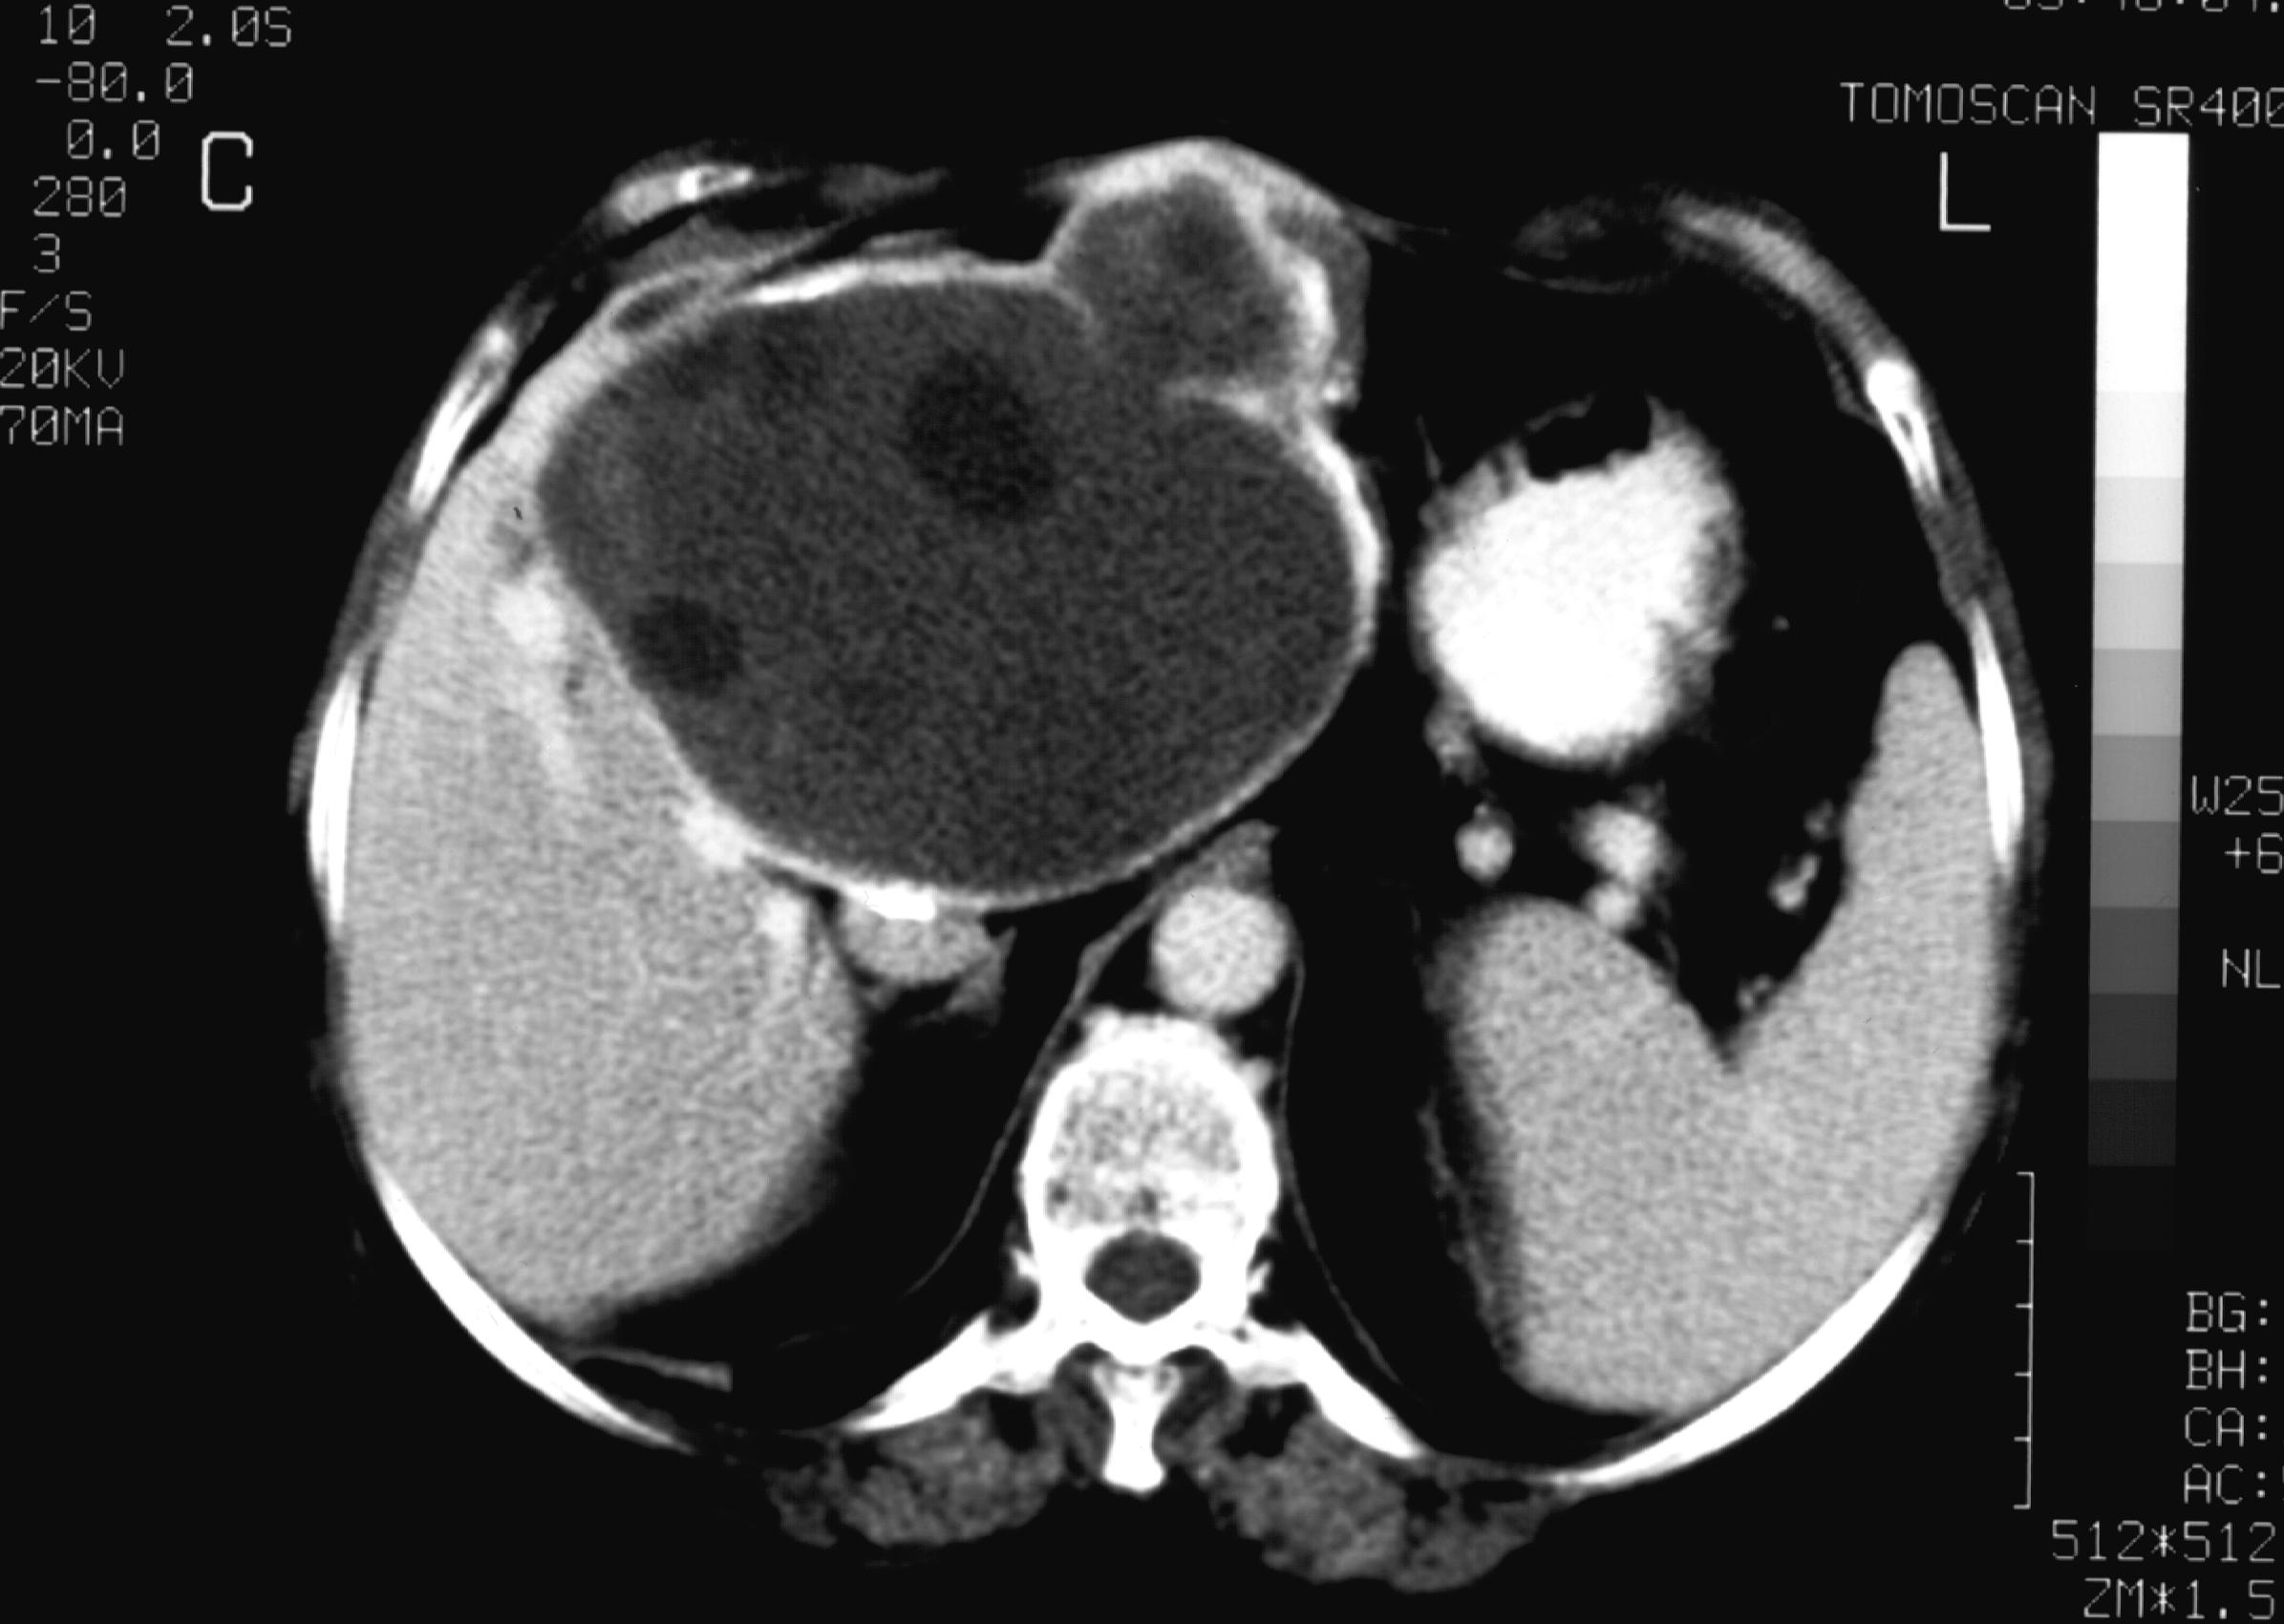

MRI is only needed in case of "atypical" hemangiomas, since ultrasound is the best imaging method for diagnosing the hemangioma. If the ultrasound finding is uncertain, dynamic CT (Figure 19, 20), afterwards nuclear imaging and biopsy are the appropriate choices.

Figure 19: Hemangioma in the liver, native CT

Figure 20: Hemangioma in the liver, contrast enhanced CT